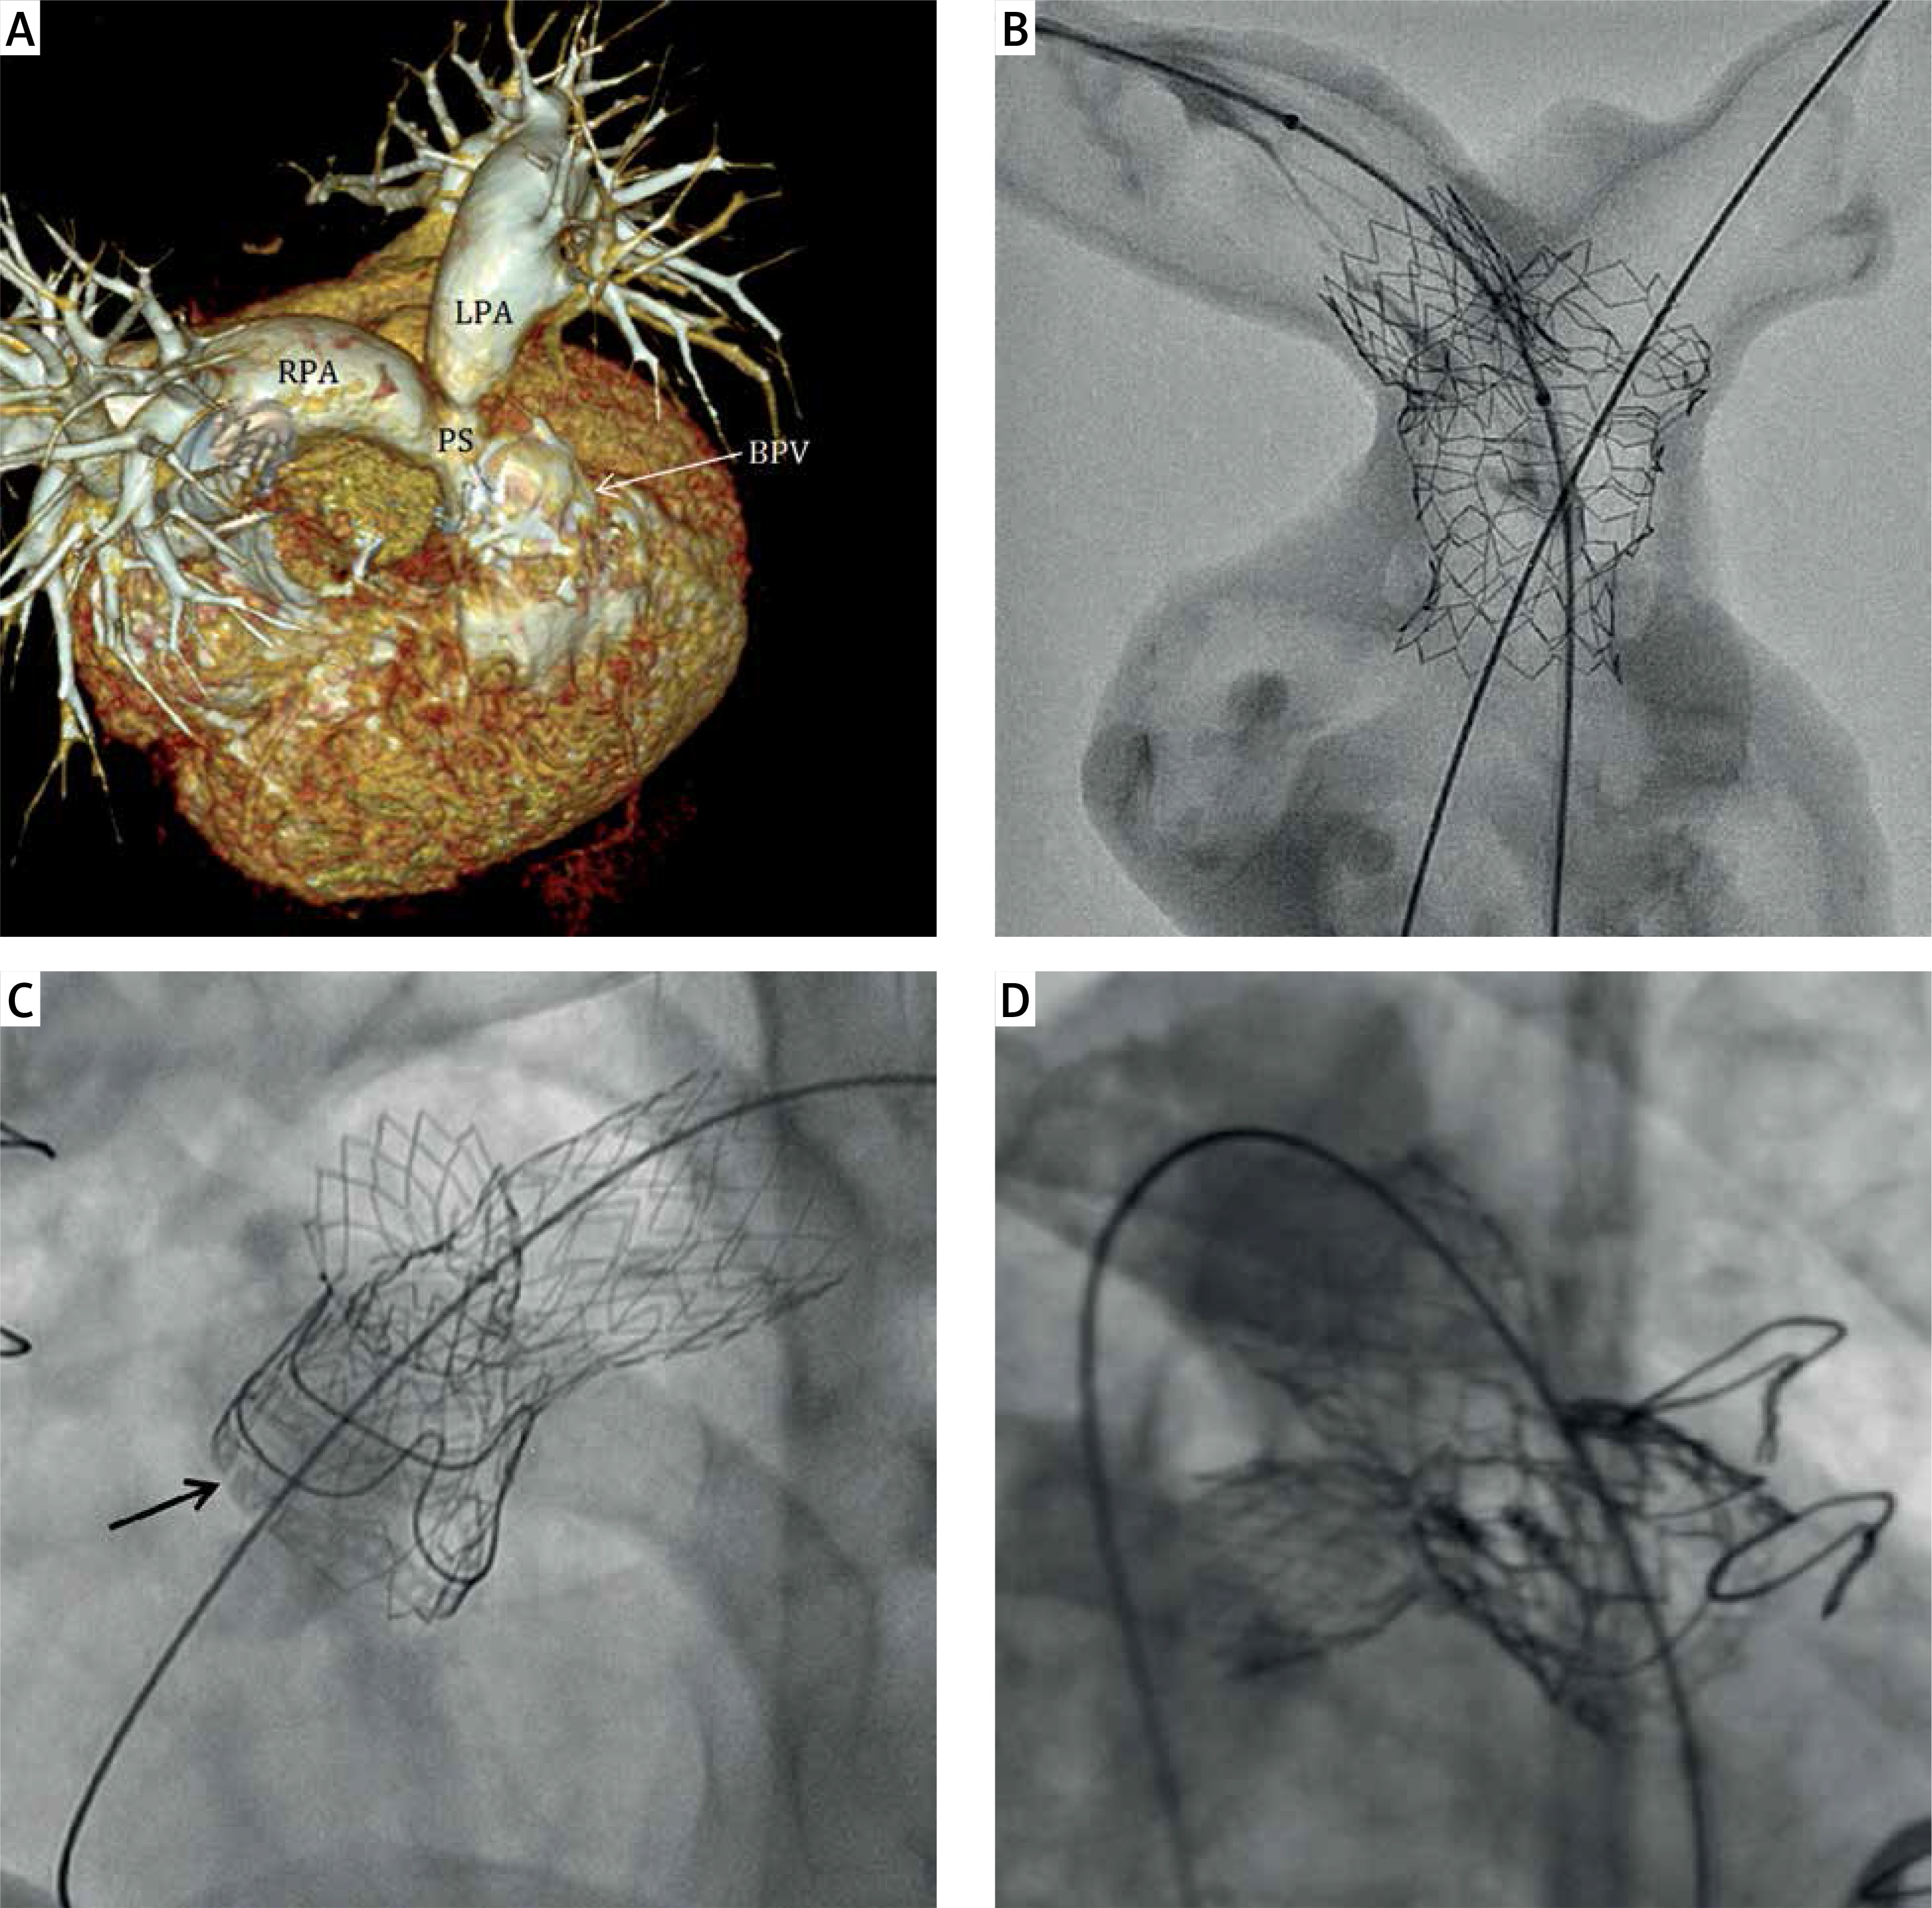

Figure 1

A – Computed tomography of a 17-year-old tetralogy of Fallot patient after bioprosthetic Edwards Magna valve (BPV) surgical replacement. Supravalvular pulmonary (PS) and bifurcation stenosis. B – Three-dimensional computed tomography-derived silicone model of the right ventricle outflow tract with supravalvular (PS) and bifurcation stenosis: 48 mm AndraStent XXL implanted into PS and LPA and through this stent’s cells a 21 mm AndraStent XXL was implanted in the RPA. C – 48 mm AndraStent XXL implanted into both PS and LPA and 21 mm AndraStent XXL implanted into RPA. Lower frame of 23 mm Magna valve cracked at 18 atm with 24 mm Atlas balloon, arrow – frame separation. D – 23 mm Edwards Sapien XT valve implanted in the upper part of a 23 mm Magna valve

RPA – right pulmonary artery, LPA – left pulmonary artery.

A PS gradient of 51 mm Hg, right-to-left ventricle pressure ratio (RV/LV) of 0.73, and a BPV ID of 19 mm were confirmed by catheterization. A 48 mm AndraStent XXL (AndraMed GmbH, Reutlingen, Germany) was implanted into the LPA, pulmonary trunk, and Magna valve on a 22 mm BIB balloon (NuMED Inc., NY, USA). The supravalvular diameter increased to 18.3 and the LPA origin increased to 16 mm. The next step was postponed for a month to enable partial stent ingrowth. After pre-dilatation with a 12 mm Atlas Gold balloon, a 21 mm AndraStent XXL on a 16 mm MaxiLD (Cordis, Florida, USA) balloon was implanted into the RPA through a semi-opened first stent scaffold. The RPA expanded to 11.4 mm. Magna valve fracture was performed 3 months later with a 24 mm Atlas balloon. The lower BPV frame cracked at 18 atm and ID increased to 22 mm (Figure 1 C). A 23 mm Edwards Sapien XT valve was subsequently implanted slightly above the Magna valve (balloon overfilled with 3 ml) (Figure 1 D). The XT valve overdilation allowed the BPV ID to be expanded to 24, the XT valve ID to 22, and supravalvular stenosis to 21 mm. The residual gradient decreased to 30 mm Hg with an RV/LV ratio of 0.39 and persisted at the supravalvular stenosis (top of the XT valve). There were no procedure-related complications during any stage. Life-long aspirin, 6 months of clopidogrel, and continuous infective endocarditis prophylaxis were administered. In a 10-month follow-up, the patient is asymptomatic with a mean PS gradient < 25 mm Hg and no PR in routine control echocardiography.